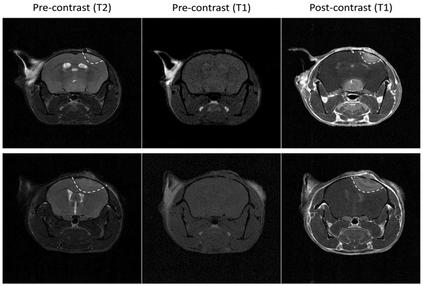

Using bioluminescence in MRI

A section highlighting novel research done in

A section highlighting novel research done in the last few years. Here you can discover how the last few years. Here you can discover how magnetic resonance imaging is enhanced magnetic resonance imaging is enhanced through the use of bioluminescence, what the through the use of bioluminescence, what the drug Pregabalin does and outlining the details drug Pregabalin does and outlining the details on a new and potentially promising trial for on a new and potentially promising for prostatecancer. prostatecancer.